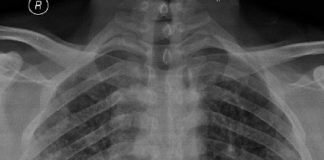

Pnömotoraks

Pnömotoraks acil serviste sık karşılaşılan, havanın akciğerden plevral boşluğa hava geçmesi ile meydana gelen bir göğüs cerrahisi acilidir. Plevral boşluktaki hava birikimi akciğere baskı...

Buzlu Cam Gönünümü

Akciğer parankim dansitesinde artış olan bölğelerde dansitenin altındaki damar ve bronş duvarları seçilebiliyorsa buzlu cam ğörünümününden, seçilemiyorsa konsolidasyondan

söz edilir. Akciğer parankimine buzlu bir camın...